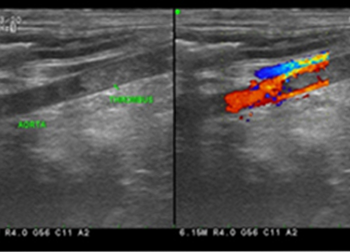

초음파(Ultrasonography)검사

-

신체에 무해한 초음파를 몸에 투사하여 간, 담낭, 비장, 췌장, 혈관계, 비뇨생식기계, 위장관을 포함한 질병의 유무, 병소의 크기와 양상을 진단하는데 필수적인 검사방법입니다. 일반적인 복강 내 장기 외에도 초음파를 통해 뇌실, 안구, 근골격계 및 관절 인대에 대한 평가를 시행하고 있습니다.